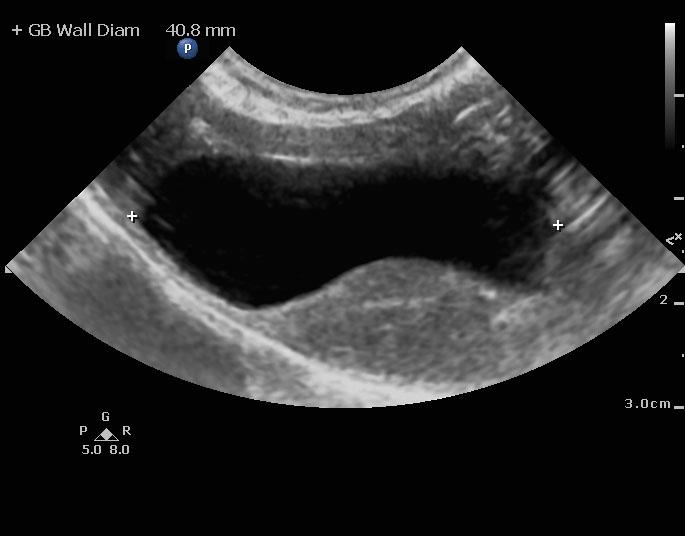

An 8-year-old spayed female Maltese dog was presented for evaluation of severely elevated pre-and post-prandial bile acids. In addition, the patient was positive for Rocky Mountain spotted fever. Seizure activity was present in the history